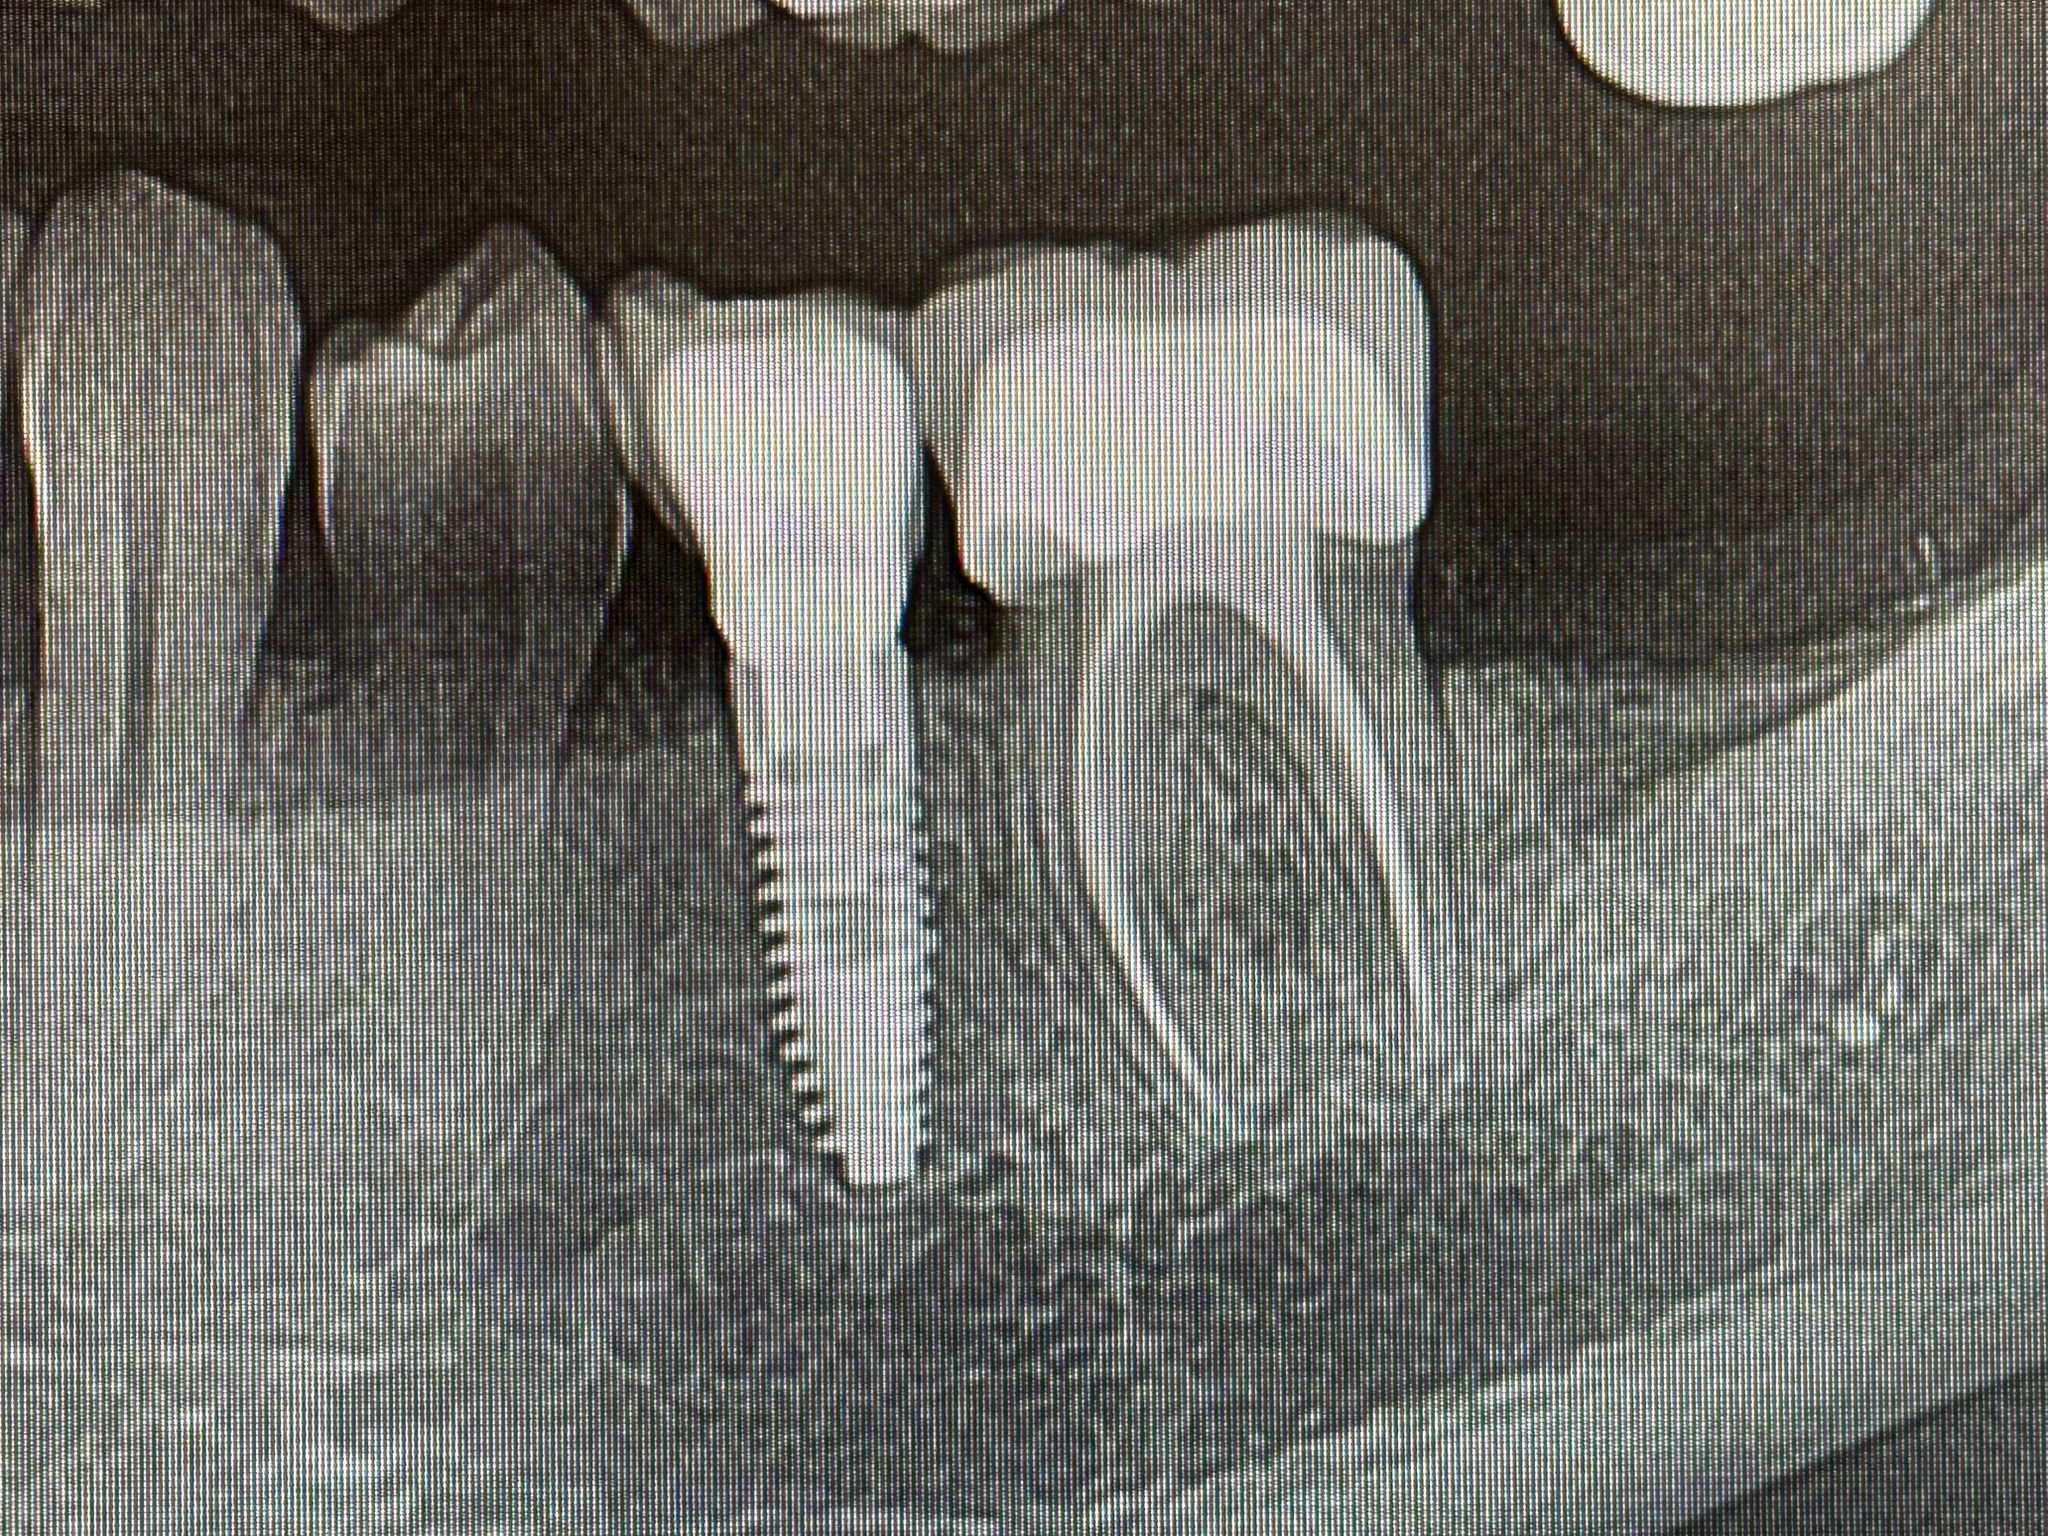

Endodonzia conservativa

Estrazione e Implantologia